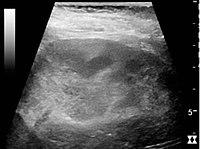

In medical imaging, the acute changes in the kidney are often examined with renal ultrasonography as the first-line modality, where CT scan and magnetic resonance imaging (MRI) are used for the follow-up examinations and when US fails to demonstrate abnormalities. In evaluation of the acute changes in the kidney, the echogenicity of the renal structures, the delineation of the kidney, the renal vascularity, kidney size and focal abnormalities are observed.[16] CT is preferred in renal traumas, but US is used for follow-up, especially in the patients suspected for the formation of urinomas. A CT scan of the abdomen will also demonstrate bladder distension or hydronephrosis. However, in AKI, the use of IV contrast is contraindicated as the contrast agent used is nephrotoxic.

16. ^ a b c d Content initially copied from: Hansen, Kristoffer; Nielsen, Michael; Ewertsen, Caroline (2015). "Ultrasonography of the Kidney: A Pictorial Review". Diagnostics. 6 (1): 2. doi:10.3390/diagnostics6010002. ISSN 2075-4418. PMC 4808817. PMID 26838799. (CC-BY 4.0) Archived 2017-10-16 at the Wayback Machine